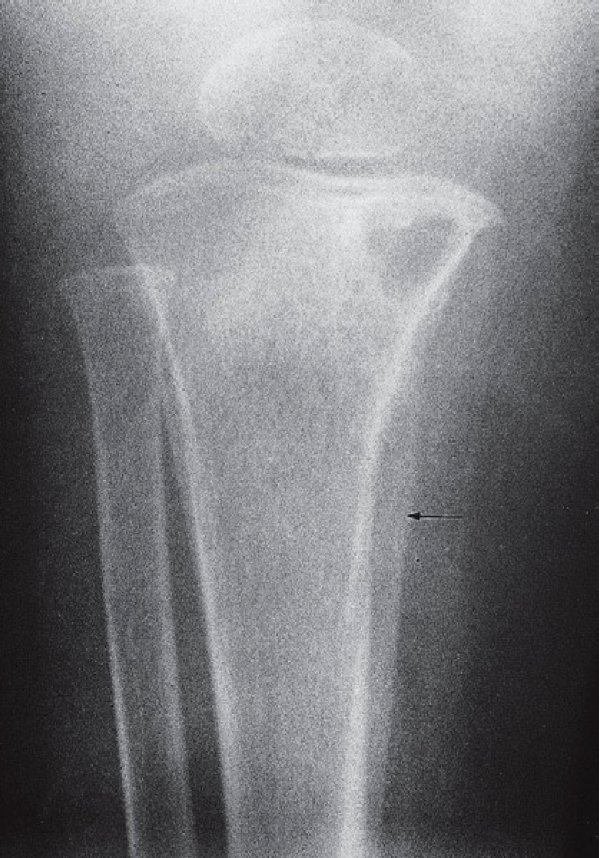

A traumatic fracture causes periosteal reaction but there is no underlying bone destruction.

Periosteal reaction (arrow) in this case osteomyelitis